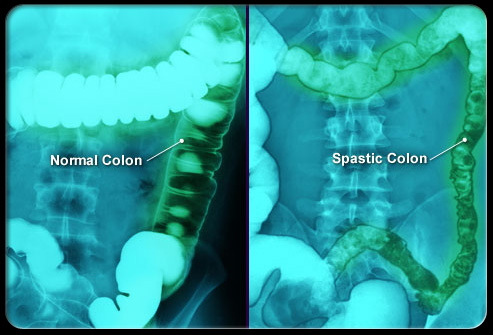

肠易激惹综合征 (IBS)

盆腔和腹部疼痛、胀气、时不时出现的便秘或腹泻通常是肠易激惹综合征(IBS)导致的。IBS是一种伴有反复发作症状的慢性功能性疾病。IBS的治疗包括调整饮食、管理压力和用药。